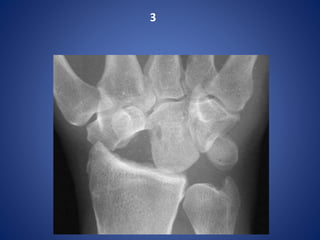

Proximal row carpectomy for scaphoid non-union

Proximal row carpectomyfor scaphoid non-union